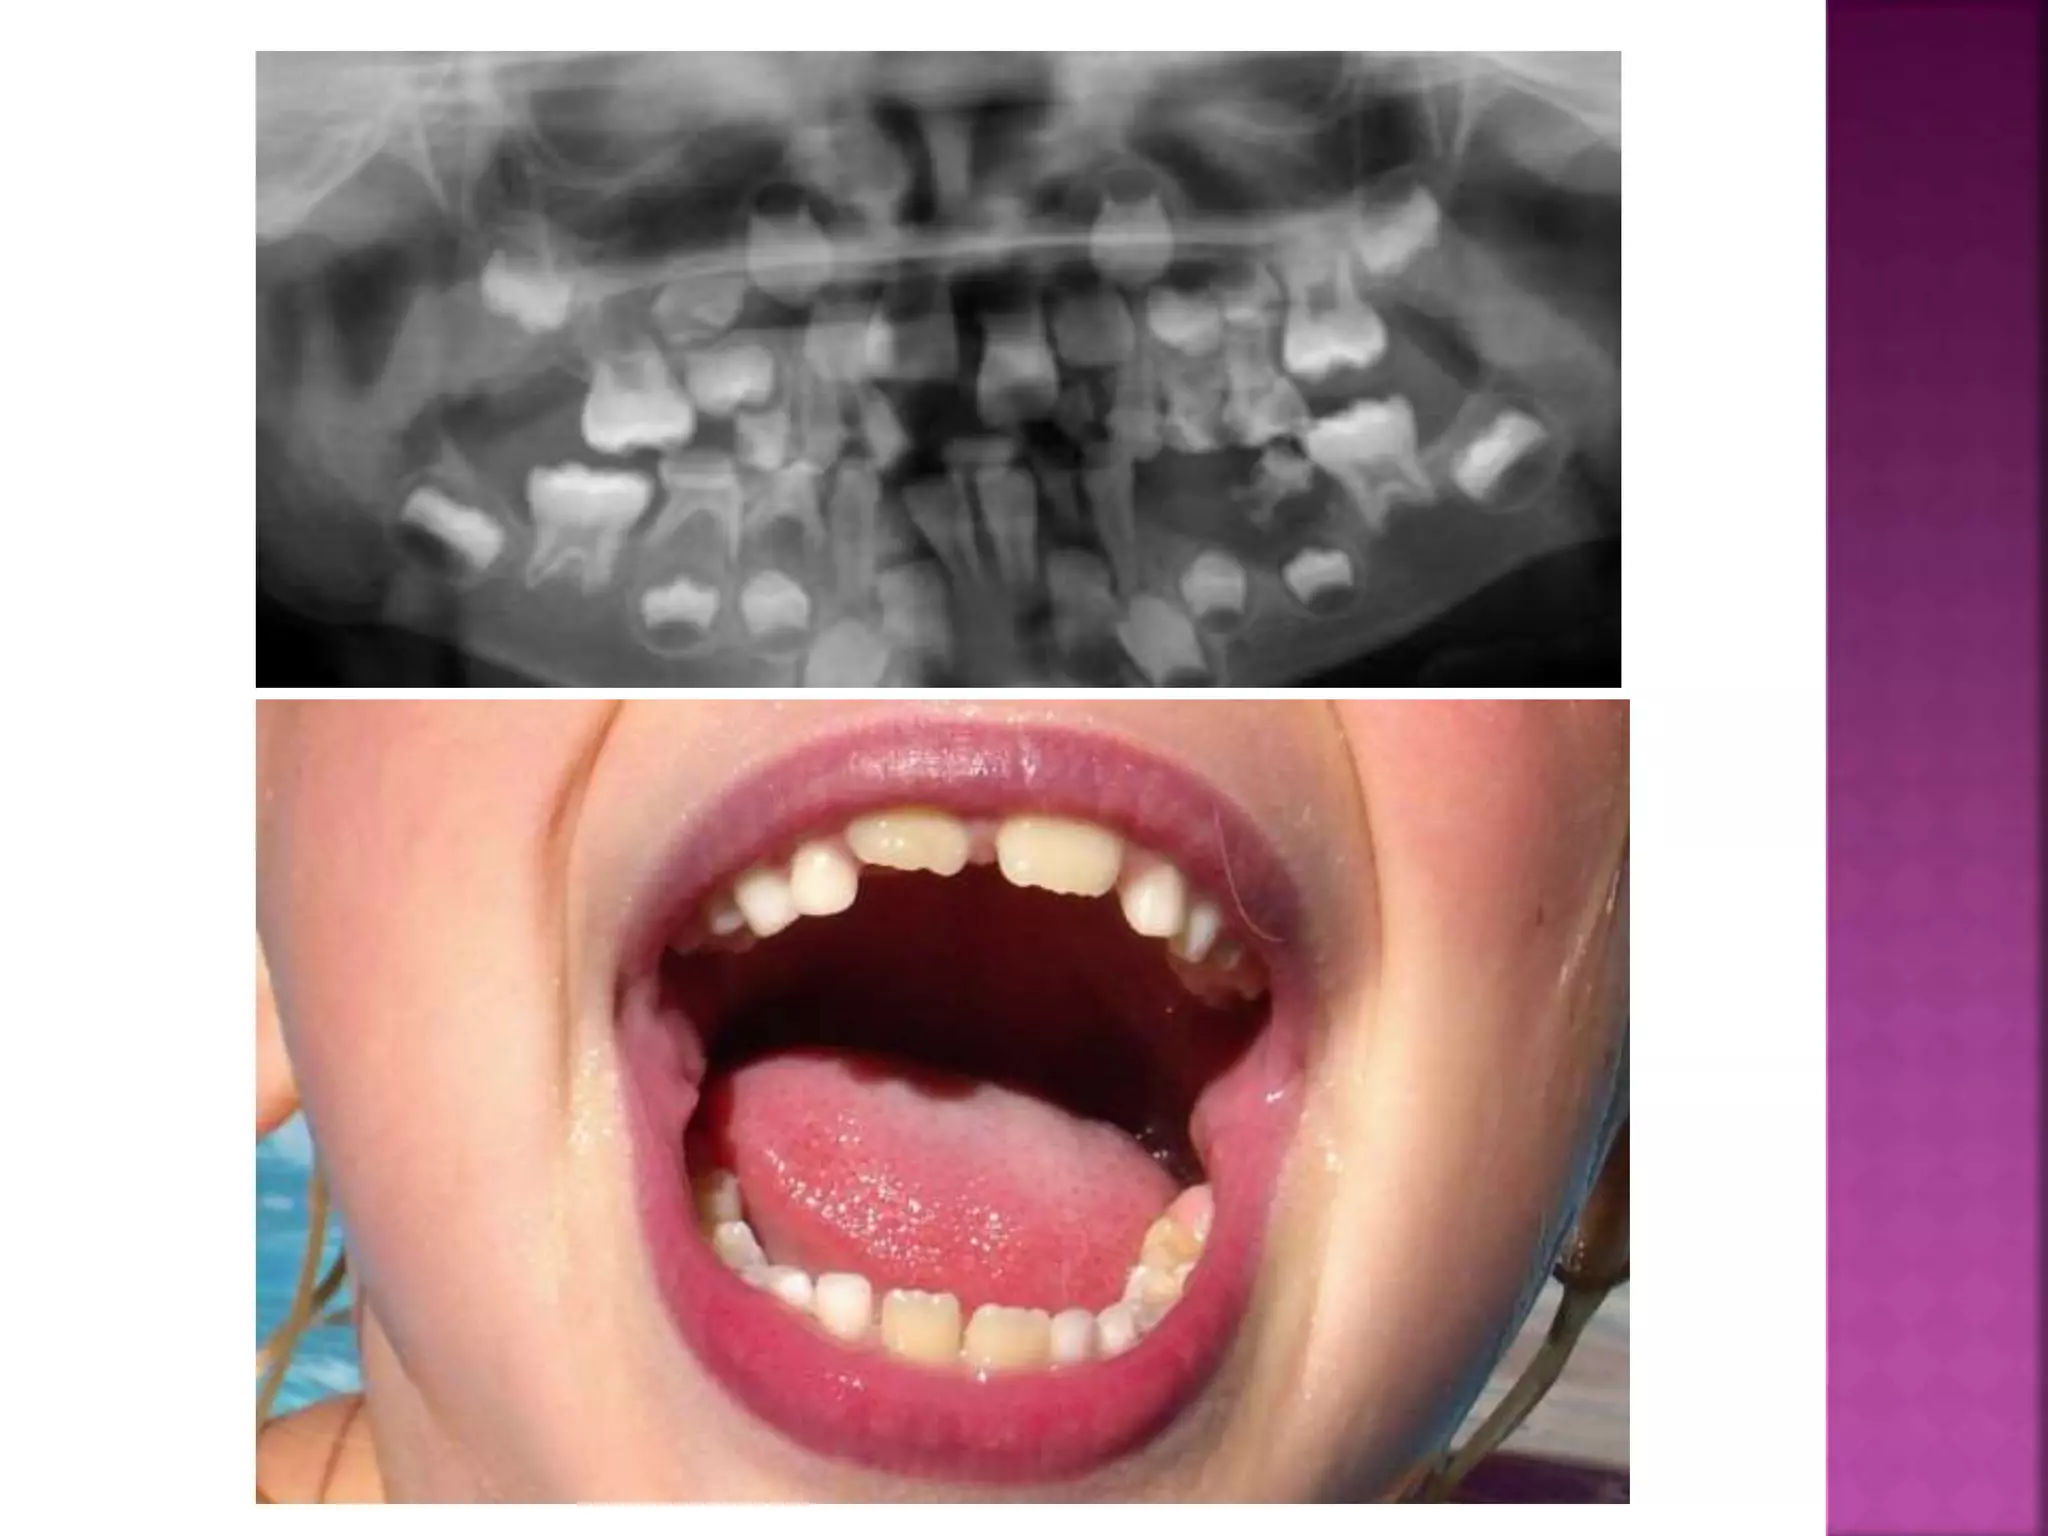

The deciduous teeth are more or less vertical in the

alveolus, so that when occlude, there is little

dislodging force ..

 When the roots of a complete permanent

dentition are examined, they show that

the degree of root curvature increase

towards the back of the mouth, i.e.,

distal inclination of the teeth axes

increases towards the end of the series

 These teeth, therefore, erupt slightly

mesially inclined, and when they come into

occlusion, they exert upon each other an

equal and opposite force.

As a result of their axial inclinations, this force will be divided

into vertical and horizontal compenents of force. The vertical

components will cancel each other and leaving just a mesial force

on all the teeth .This mesial force is called the anterior

component of force which transmits to the teeth by approximal

contact.